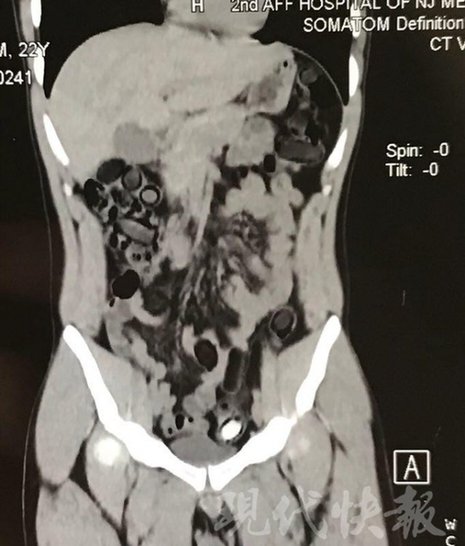

運毒小伙:希望被判處死刑

由于毒品在體內一旦泄露有可能致命,警方第一時間將阿永帶到醫(yī)院進行檢查。CT 掃描的結果顯示,阿永體內布滿了密密麻麻的白色圓柱狀固體,就像一粒粒的蠶蛹。在南京市公安局鼓樓分局二板橋派出所,阿永分四次排出了毒品,毛重369.99克。經訊問,阿永交代了自己全部的犯罪事實。目前,阿永已被刑事拘留。